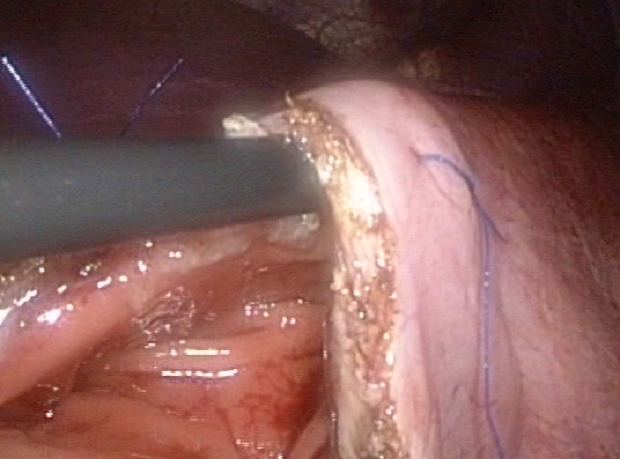

- Distal pancreatectomy (for removal of pancreas tumor)

- Whipple operation (for removal of pancreas cancer)